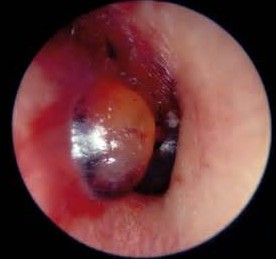

3、鼓室成型術(shù): 中耳炎治療方法中比較完善的體系就是鼓室成形術(shù)。仁品醫(yī)院采用國際先進的鼓室成型手術(shù)體系,結(jié)合多年豐富的臨床經(jīng)驗,有效根除中耳炎等耳科疾病。目前已成功進行耳病鼓室成形、聽力重建等手術(shù)一萬多例,分別取得了良好的治療效果,為耳病患者帶來了健康福音,獲得了眾多治療患者的高度好評。